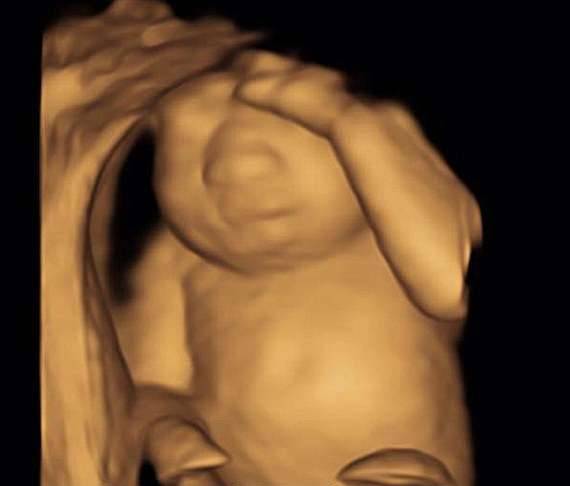

▼医生检查后发现,Keri腹中的宝宝身体健康,各项指标都很正常,但大脑畸形,没有存活的希望,建议她直接堕胎。

▼其实做出这个决定,对Keri来说并不容易。在接下来的怀孕过程中,她会感觉到胎儿的活动,女儿的小脚会踢打她的肚子,女儿的心跳会让她痛心。